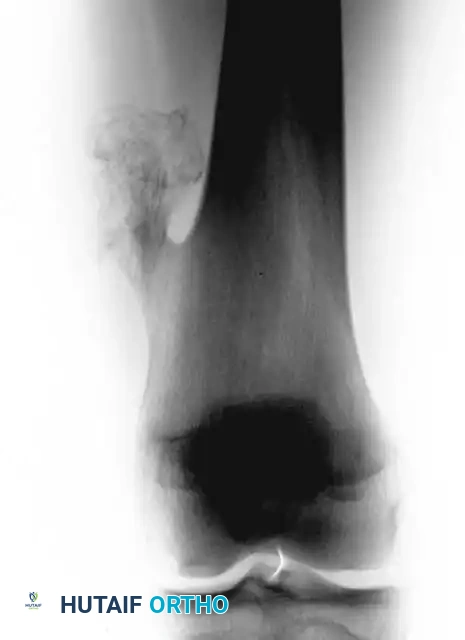

Plain radiographs are the cornerstone of diagnosis. Enchondromas present as well-circumscribed, benign-appearing radiolucent lesions with characteristic intralesional calcifications. These calcifications are classically described as "stippled," "punctate," "flocculent," or "popcorn-like" rings and arcs, representing the enchondral ossification of the hyaline cartilage lobules.

Anteroposterior radiograph of the distal femur showing a calcified lesion without cortical destruction, consistent with an enchondroma.

Lateral radiograph of the same distal femur lesion.

In the small bones of the hands and feet, enchondromas frequently cause considerable endosteal erosion and expansion of the overlying cortex, leading to a thinned, "eggshell" appearance. However, in more proximal locations (e.g., proximal humerus, distal femur), deep endosteal erosion—defined as scalloping exceeding two-thirds of the cortical thickness—is a highly suspicious radiographic hallmark of chondrosarcoma.